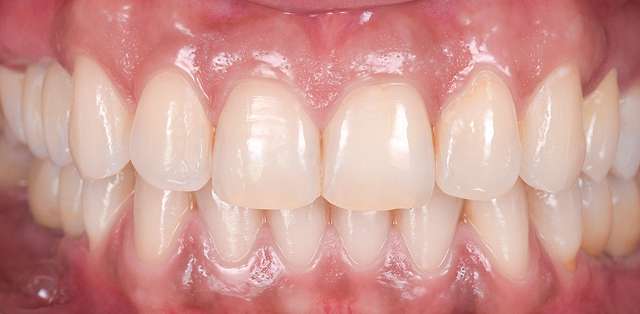

For optimal esthetic results, the final design must always be the refference for the surgery. This design together with the CBCT of the patient are compiled to find the ideal position of the dental implants.

Guided surgery is safe and precise. A surgical guide is recommended in difficult or complex cases, to minimise risks and complications.

When implant therapy is performed with guided surgery, the surgery itself is simpler, and trauma is reduced especially for the soft-tissues. Overall we can achieve faster healing and better post-op comfort.